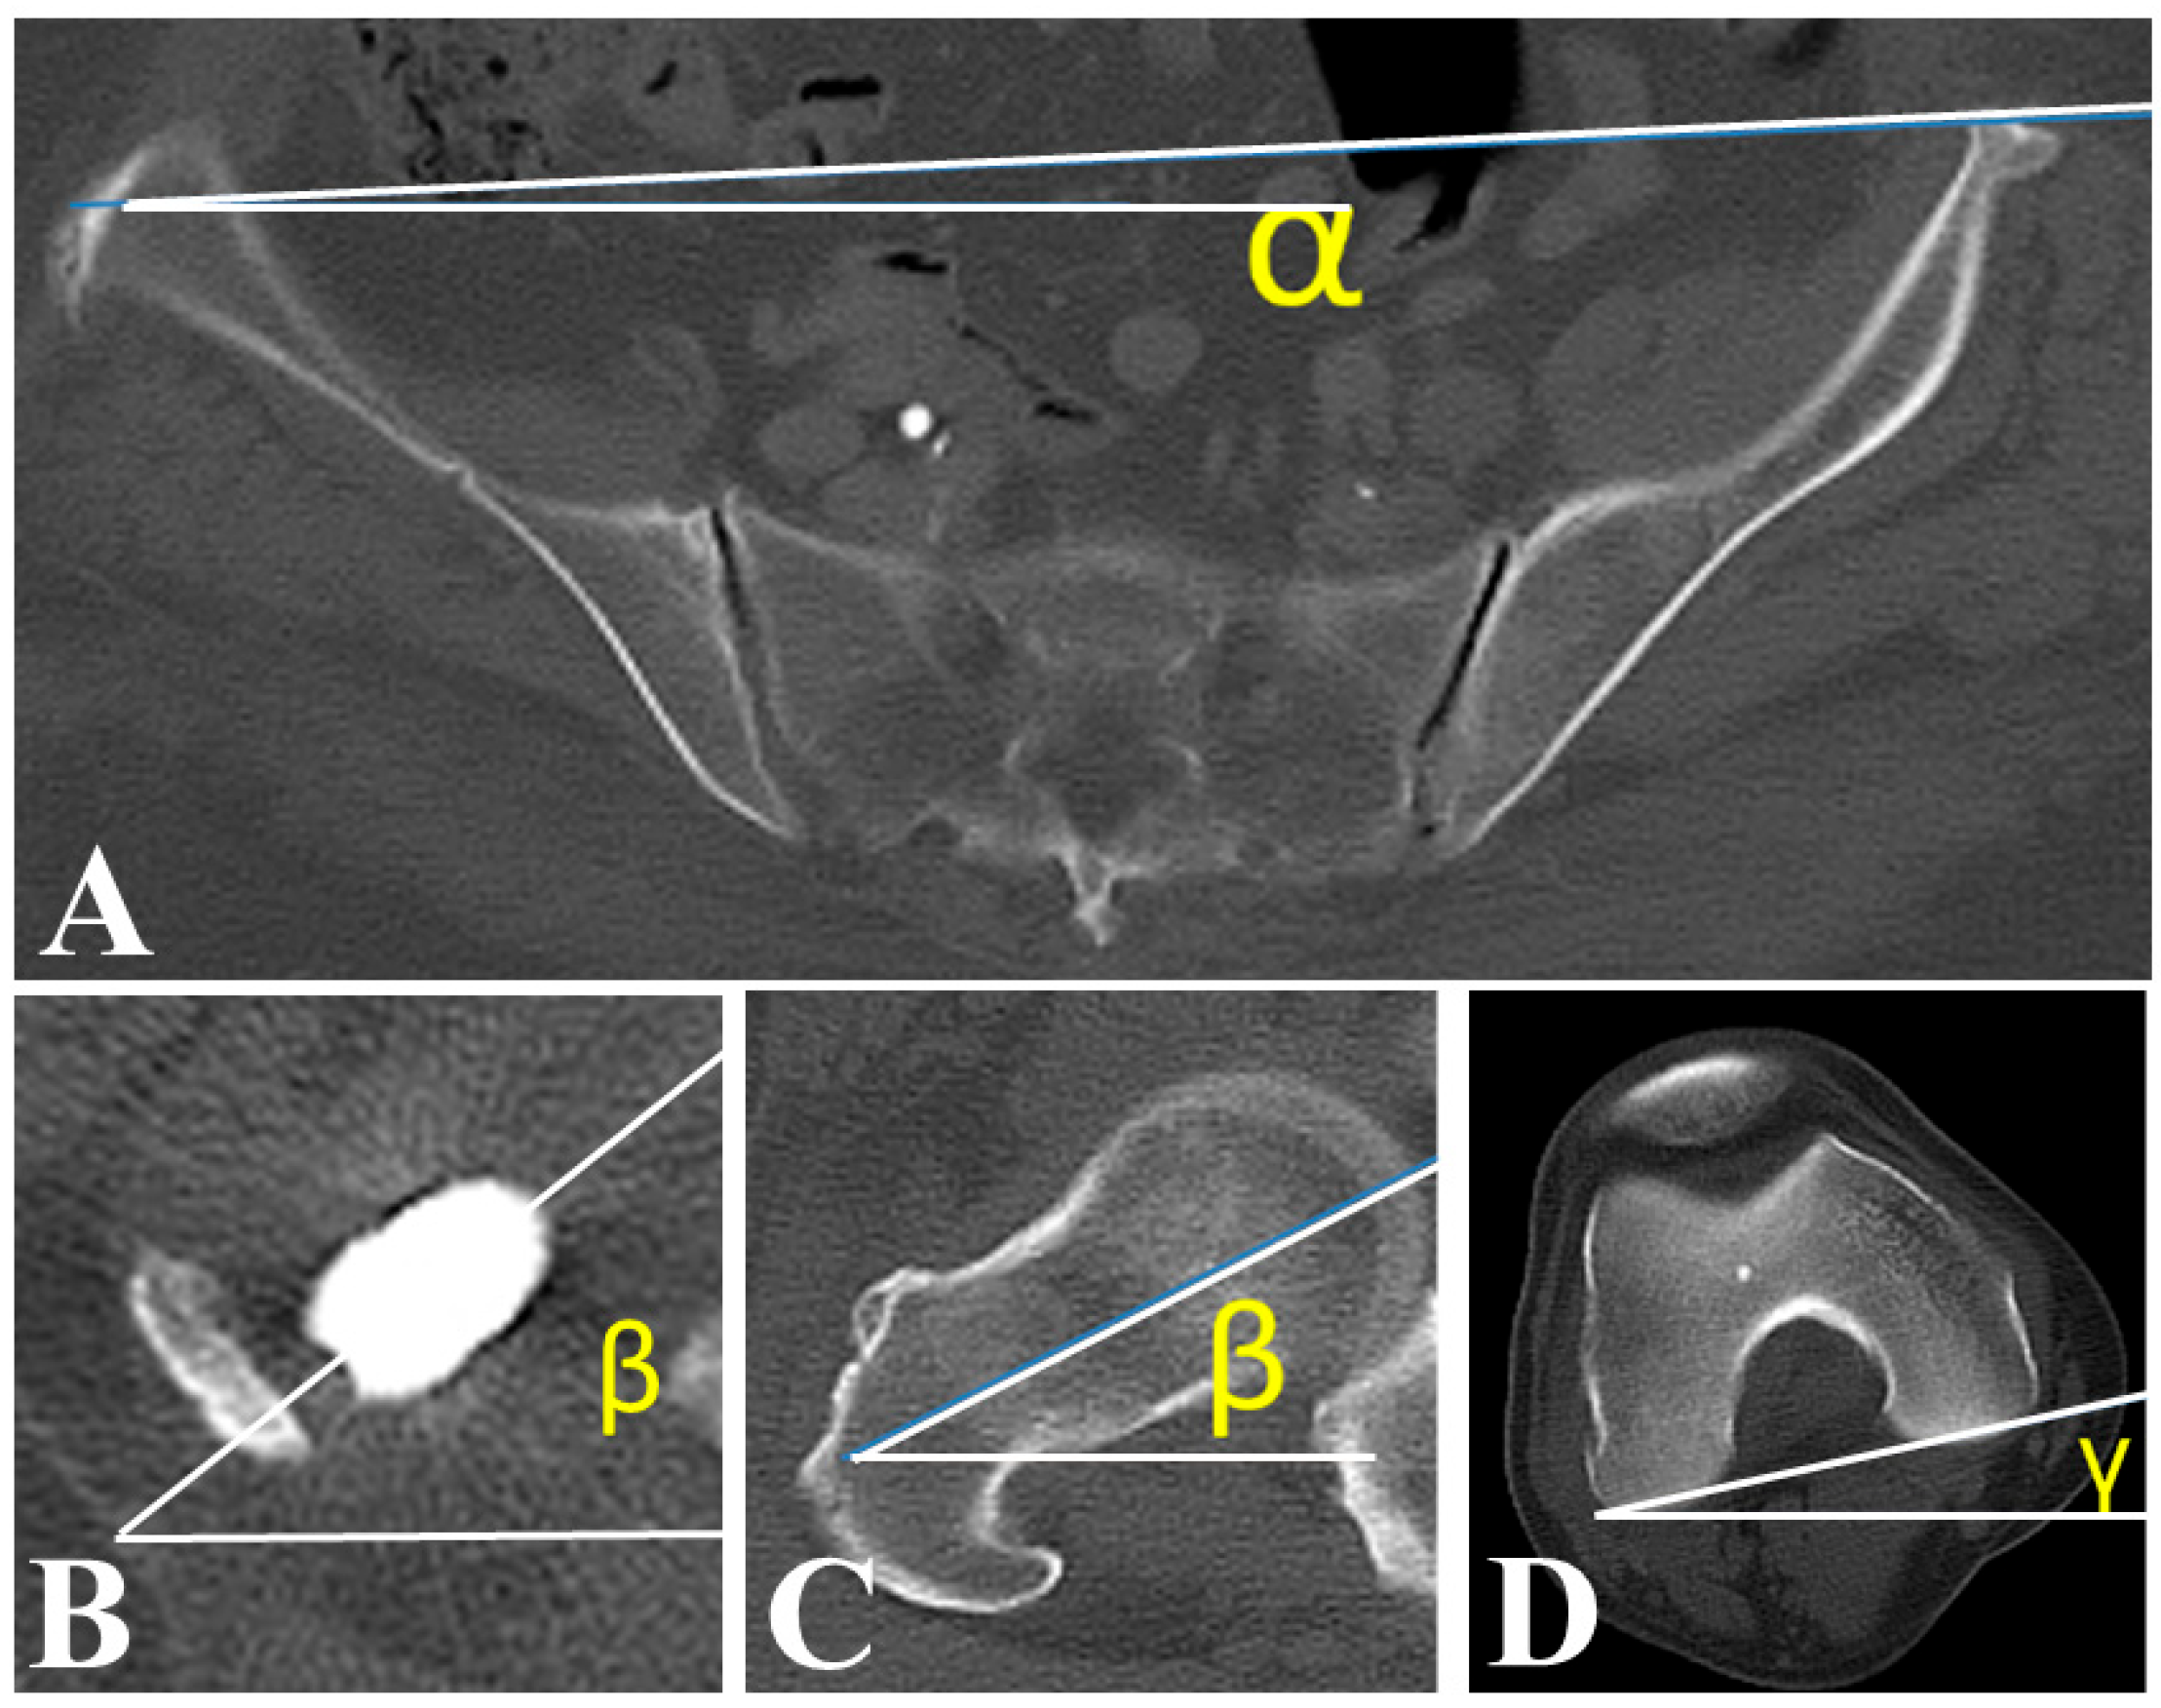

| Postoperative anatomical SA (°) | 17.0 ± 17.7 |

| Postoperative FR (°) | 14.4 ± 22.6 |